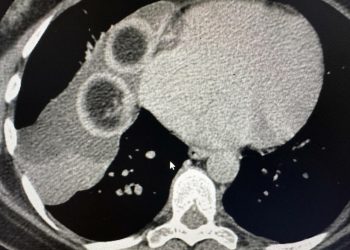

Хирурги из Республиканской клинической больницы спасли жизнь 31-летней жительнице Удмуртии, Евгении Афанасьевой, столкнувшейся с редким и опасным диагнозом — альвеококкоз ...

Огромный ком червей из печени девушки достали врачи РКБ. Об этом сообщает пресс-служба медицинского учреждения. Как стало известно, девушку доставили ...